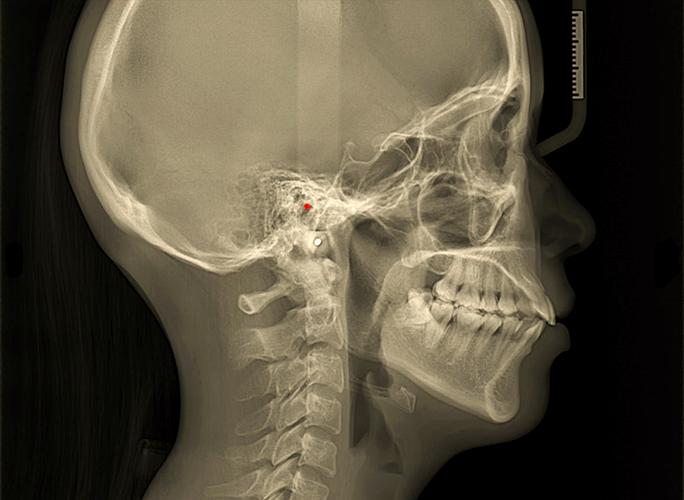

正畸头影测量是口腔正畸学中利用X线头颅定位片对颅颌面结构进行定性与定量分析的核心技术,而普通正畸头影测量(简称“普特正畸头影测量”)作为临床应用最广泛的基础方法,通过二维影像评估骨骼、牙齿及软组织的形态与位置关系,为错畸形诊断、治疗方案设计及疗效评价提供客观依据。

普特正畸头影测量的准确性依赖于对颅颌面解剖标志点的精确定位,以及基于这些点的标准化测量,常用标志点可分为骨骼标志点、牙齿标志点和软组织标志点三大类,测量项目则包括角度、线距、比例等多种类型。

(一)常用标志点定义

| 类别 | 标志点 | 定义/位置 |

|---|---|---|

| 颅底标志点 | Sella (S) | 蝶鞍中心,颅部的参考中心点 |

| Nasion (N) | 鼻额缝的最前点,代表颅部与前部的交界 | |

| 上颌标志点 | A点 (Subspinale) | 上颌骨前壁与牙槽突的最凹点,反映上颌骨相对颅部的位置 |

| Orbitale (Or) | 眶下缘最低点,与构成眶耳平面(FH平面)的关键点 | |

| 下颌标志点 | B点 (Supramentale) | 下颌骨前壁与牙槽突的最凹点,反映下颌骨相对颅部的位置 |

| Pogonion (Pg) | 颏部最前点,代表下颌骨颏部的突度 | |

| Gnathion (Gn) | 下颌骨下缘最下点,垂直参考的重要标志 | |

| 牙齿标志点 | U1 (上颌中切牙) | 上颌中切牙切缘中点或根尖尖点(根据测量需求选择) |

| L1 (下颌中切牙) | 下颌中切牙切缘中点或根尖尖点 | |

| 软组织标志点 | Ns (软组织鼻根) | 软组织鼻额缝的最前点 |

| Pg' (软组织颏前点) | 软组织颏部最前点 |